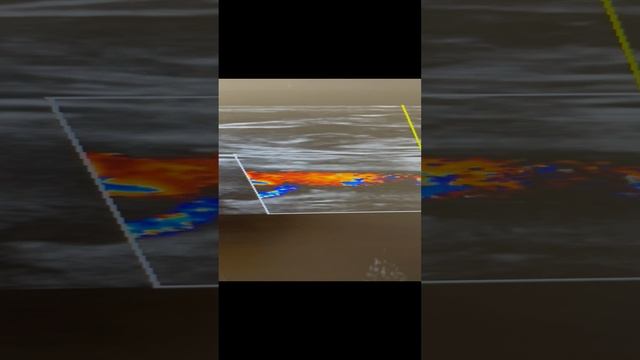

Варикоцеле 4 ст. Контроль Узи перед операцией. смотреть онлайн

Варикоцеле 4 ст. Контроль Узи перед операцией.

Часть 1. Варикоцеле 4 ст. Узи паховой области. Сосудистый хирург. Флеболог Москва смотреть онлайн

Часть 1. Варикоцеле 4 ст. Узи паховой области. Сосудистый хирург. Флеболог Москва